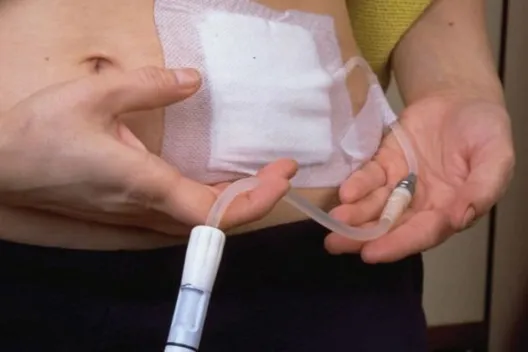

Diálise Peritoneal na Doença Renal Policística: existe algum motivo para não indicar?

Diálise Peritoneal na Doença Renal Policística: existe algum motivo para não indicar?

A DRPAD não é contraindicação à DP — e, na prática, muitos pacientes têm resultados comparáveis à hemodiálise. O “porém” está na mecânica: rins/hepatomegalia podem reduzir tolerância a volumes, aumentar risco de hérnias e extravasamentos, e piorar desconforto respiratório. Com técnica adequada (cateter presternal ou lateral, volumes menores, cicladora noturna e decúbito supino), a maioria das barreiras é contornável. Neste post, revisamos quando a DP é ótima, quando exigir cautela e como ajustar a prescrição para segurança e qualidade de vida.